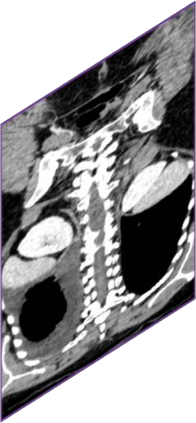

Due to the constraints of the imaging device and high cost in operation time, computer tomography (CT) scans are usually acquired with low intra-slice resolution. Improving the intra-slice resolution is beneficial to the disease diagnosis for both human experts and computer-aided systems. To this end, this paper builds a novel medical slice synthesis to increase the between-slice resolution. Considering that the ground-truth intermediate medical slices are always absent in clinical practice, we introduce the incremental cross-view mutual distillation strategy to accomplish this task in the self-supervised learning manner. Specifically, we model this problem from three different views: slice-wise interpolation from axial view and pixel-wise interpolation from coronal and sagittal views. Under this circumstance, the models learned from different views can distill valuable knowledge to guide the learning processes of each other. We can repeat this process to make the models synthesize intermediate slice data with increasing inter-slice resolution. To demonstrate the effectiveness of the proposed approach, we conduct comprehensive experiments on a large-scale CT dataset. Quantitative and qualitative comparison results show that our method outperforms state-of-the-art algorithms by clear margins.